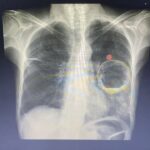

Olá pessoal, eu sou Dr. Massau e sejam bem-vindos ao blog Méditerranée. Hoje vamos aprender uma maneira rápida de interpretar o raio-X de tórax. Esse é um método bastante didático e útil para médicos emergencistas, já que temos que analisar rapidamente um grande número de exames em um único plantão. Cada médico tem sua metodologia de análise, porém é importante lembrar que uma boa sistematização nos ajuda a não deixar passar despercebido detalhes ou pequenas alterações que podem fazer a diferença, ainda mais se tratando de casos de emergência. Então vamos lá, vamos analisar uma radiografia de tórax seguindo os passos MILHÃO.

Na letra A, vamos analisar rapidamente as vias aéreas. No caso, somente a traqueia. Vamos analisar se ela está centrada e perceber a presença de calcificação no lume na parte inferior da traqueia. Notamos a carina traqueal, que marca a divisão dos brônquios fontes. Na letra B, de “brônquios”, vamos analisar os brônquios e pulmões. Aqui, dá pra perceber que temos os brônquios fontes direito e esquerdo. O direito é sempre mais verticalizado do que o esquerdo. Em sequência, já avaliamos o parênquima pulmonar em busca de infiltrados ou alterações da transparência pulmonar. Normalmente, notamos que o parênquima apresenta a trama peribrônquica, que nada mais é do que as ramificações dos brônquios e seus respectivos vasos. Notamos também que a trama peribrônquica vai diminuindo quando chegamos na periferia.

Na letra C, de “coração”, vamos analisar o coração e os vasos da base, e aproveitar para ver se o mediastino não está alargado. O coração tem tamanho normal. Se o diâmetro da silhueta cardíaca for menor do que a metade do diâmetro interno do tórax, não temos cardiomegalia. Agora vamos analisar de perto os contornos da silhueta cardíaca e dos vasos da base.

Na letra D, de “diafragma”, vamos analisar o contorno das bordas do músculo diafragma. Geralmente, o contorno do lado direito é mais elevado e mais nítido, por causa do fígado que está situado logo abaixo. Quando existe perda do contorno do diafragma ou abaulamento, devemos pensar em acometimento no parênquima pulmonar adjacente. Outro ponto importante é analisar a região lateral, conhecida como seios costofrênicos. Quando eles estão livres, podemos ver todo o contorno do diafragma até a parede torácica interna. Se houver obliteração dessa região, devemos pensar em derrame pleural ou acometimento do parênquima pulmonar adjacente.

A próxima letra é a E, de “esqueleto”. Nessa etapa, vamos analisar todo o arcabouço ósseo torácico. Começamos olhando todos os arcos costais, percorrendo da região posterior até a região anterior. Na região próxima da articulação costocondral, a estrutura óssea fica cada vez menos visível, sendo que na região mais próxima da articulação, ela começa a ficar com tecido cartilaginoso e por isso menos perceptível no raio-X. Feito uma inspiração profunda e de modo adequado, conseguimos ver entre 9 a 10 arcos costais. Aproveitamos e olhamos também se as linhas ósseas da clavícula, escápula e úmero estão preservadas, e se não existe indícios de fratura ou lesão.

A próxima letra é a F, de “fat”, que significa gordura em inglês. Aqui, analisamos o subcutâneo e as partes moles. Vamos avaliar se existe indícios de enfisema subcutâneo, que é basicamente a existência de ar no subcutâneo, uma condição que pode acontecer nos traumatismos torácicos ou mesmo complicações de procedimentos médicos. Aqui vale lembrar que o contorno das mamas nas mulheres pode atrapalhar a análise mais detalhada do parênquima pulmonar no primeiro andar, devido à interposição. Por isso, é importante avaliarmos também a incidência em perfil do raio-X de tórax.

Por último, temos a letra G, de “gadget”, que significa dispositivo em inglês. Nessa etapa, analisamos os tubos, catéteres, sondas e outros dispositivos. Verificamos se estão posicionados adequadamente e se não existem complicações relacionadas.